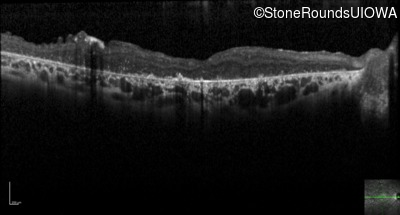

Optical Coherence Tomography - Right - Count Fingers 3'

Exemplar / OCT Stack

OCT Stack